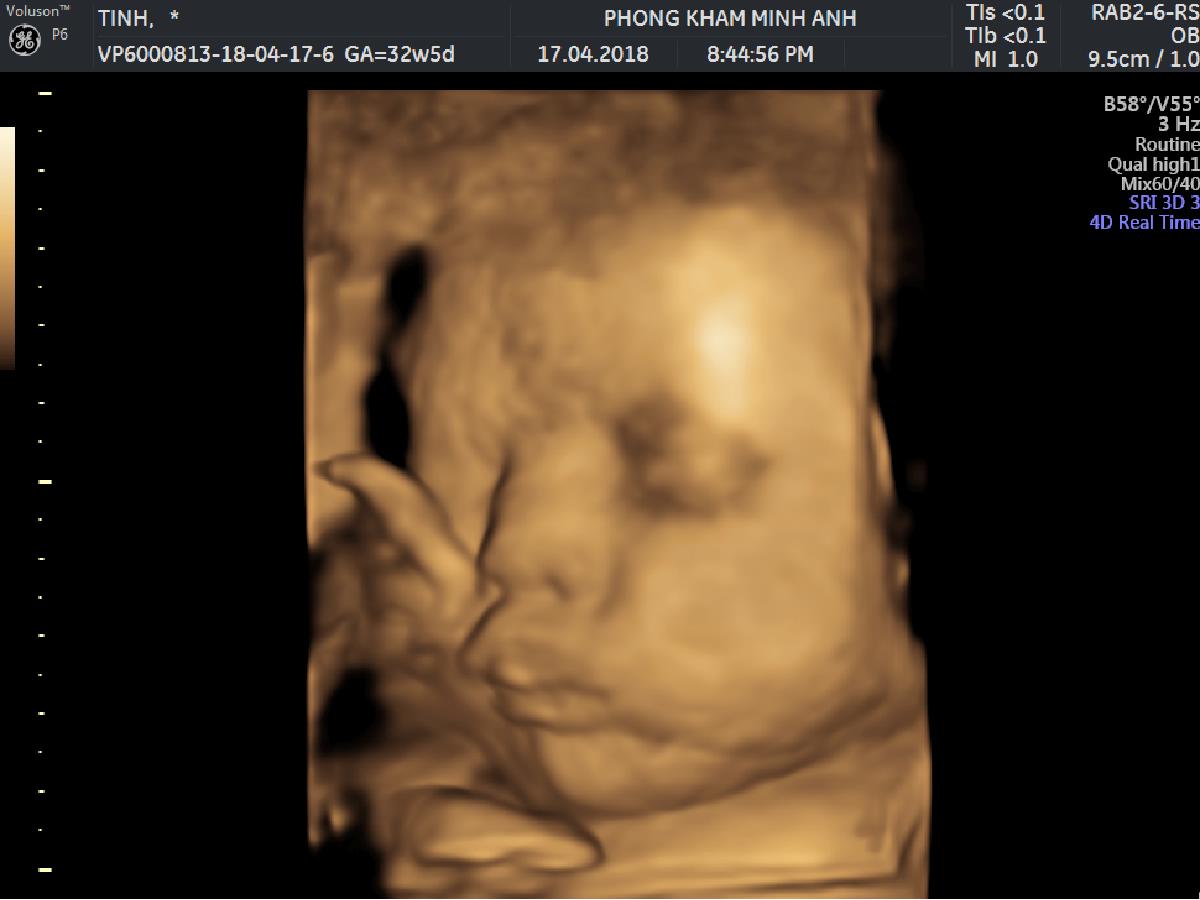

Bạn đã bao giờ thấy em bé mở mắt ngay khi còn trong bụng mẹ chưa???❤️❤️❤️???

Th7 05, 2018Các mẹ cho ý kiến gì về ảnh của con?

Hình ảnh siêu âm 4D của sản phụ Lệ Quyên, 1 trong những sản phụ đã đến khám và nhận quà tại phòng khám Sản phụ khoa Minh Anh Share this...